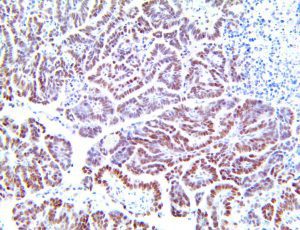

The first cytokines released are interleukin 1β (IL-1β) and tumor necrosis factor-α (TNF-α), which attract a variety of circulating white blood cells (WBCs) to the infection site, including neutrophils, monocytes, macrophages, and natural killer (NK) cells. This response, along with the antipathogenic chemicals released by these cells (i.e., complement), comprise the innate immune response. These cells directly attack the invading pathogen and also release additional cytokines, chief among them interleukin-1 and 6 (IL-6). IL-6 is essential for invoking the adaptive immune response, which calls T-cells, B-cells, and T helper (Th) cells to the infection site. IL-6 also stimulates further recruitment, proliferation and activation of macrophages.

It is the ICU physician who is most likely to witness one of the deadliest manifestations of the abnormal immunological response, the cytokine storm syndrome (CSS). This response is also referred to by some as the cytokine release syndrome (CRS). CSS is characterized by continuous activation and expansion of macrophage and lymphocyte populations, which secrete large amounts of cytokines, causing the cytokine storm. This massive cytokine release is akin to hemophagocytic lymphohistiocytosis (HLH) disease, a syndrome characterized by initial unchecked and persistent activation of cytotoxic T lymphocytes and NK cells.

This activation induces inflammatory monocytes to highly express IL-6, starting a localized and then systemic cascade effect that results in hyperproduction of IL-6, which accelerates the inflammatory process. Because IL-6 also increases vascular permeability, excessive levels cause blood vessels to become very leaky. This, along with clotting factors released from vascular endothelial cells, stimulates the coagulation cascade, resulting in microthrombosis (tiny clots), which leads to ischemia and tissue death of the kidney, intestines, heart, liver, brain and extremities.